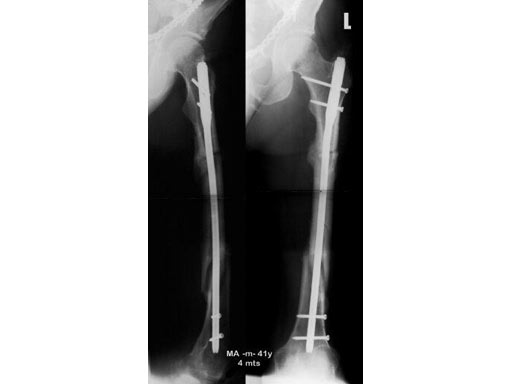

41- year- old male; accident with a motorbike.